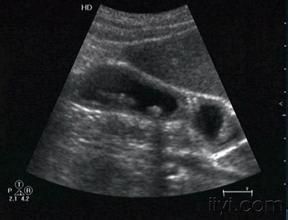

本病臨床明確診斷較為困難,Raghavendra認為超聲對膽囊腺肌病的診斷優於X線檢查,隨著超聲顯象儀解析度的提高和超聲診斷醫師的臨床經驗的積累,國內已有許多超聲診斷膽囊腺肌病的報告。膽囊腺肌病的聲象圖特點:

(1)膽囊壁增厚,呈瀰漫性,節段性改變或局限性改變。

(2)增厚的膽囊壁內,可見無回聲暗區或回聲增強區(膽固醇沉積)。

(3)合併壁間結石和膽囊結石,可出現相應的改變。